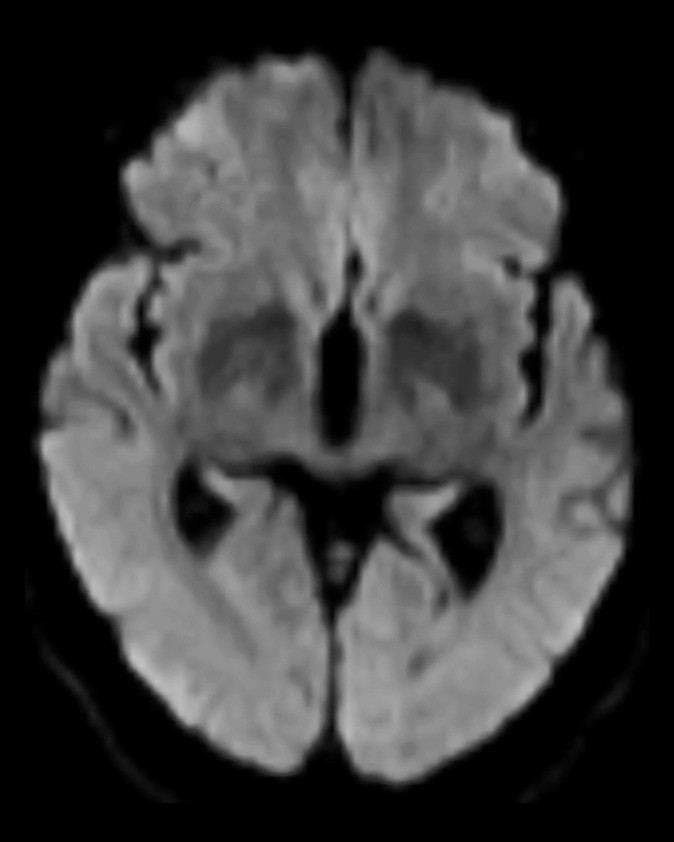

MR caput (T1- og T2-vektede sekvenser, FLAIR-sekvenser og diffusjon med ADC-verdier (apparent diffusion coefficient)) utført rett etter CT-undersøkelsen viste som tidligere uspesifikke T2- høysignal lesjoner, men ingen nytilkomne forandringer (figur 2). Det var ingen diffusjonsrestriksjon, som er forventet ved ferskt hjerneinfarkt (3).

På pasientens CT-bilder var det retensjon av kontrast i synsbarken på begge sider. CT-bildene var gjort uten kontrast, så den synlige kontrasten måtte være fra konvensjonell cerebral angiografi gjort to timer tidligere. CT-angiografi viste åpne kar. På MR var det ingen nytilkomne signalforandringer. De kliniske symptomene sammen med bildefunnene passet dermed ikke med cerebral iskemi på bakgrunn av tromboembolisme eller karspasmer.

Dette er en eksklusjonsdiagnose. MR caput og eventuelt CT caput med CT-angiografi er indisert for å utelukke blødning eller iskemisk årsak til synsaffeksjon. MR kan være negativ eller vise høysignal på T2- og FLAIR-signaler som ved vasogent ødem. CT kan vise normale funn eller kontrastoppladning oksipitalt. CT-angiografi fremstiller åpne kar uten spasmer.